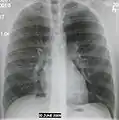

Left upper lobe pneumonia with a small pleural effusion.